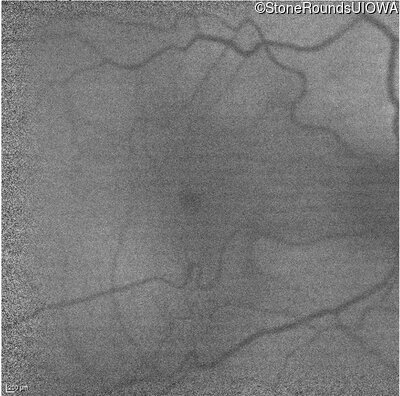

Infrared Fundus Photograph - Right - 20/200 sc

Exemplar